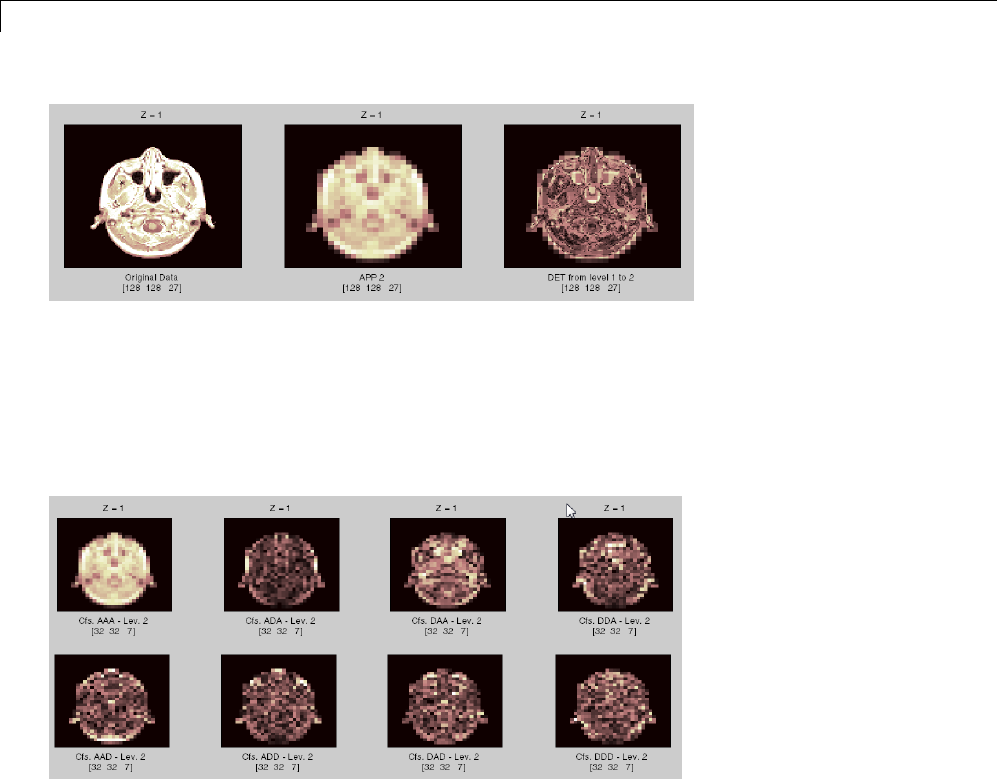

Three-Dimensional Discrete Wavelet Analysis ........ 3-181

Performing Three-Dimensional Analysis Using the

Command Line ................................. 3-181

Performing Three-Dimensional Analysis Using the

Graphical Interface .............................. 3-182

Importing and Exporting Information from the Graphical

Interface ...................................... 3-189